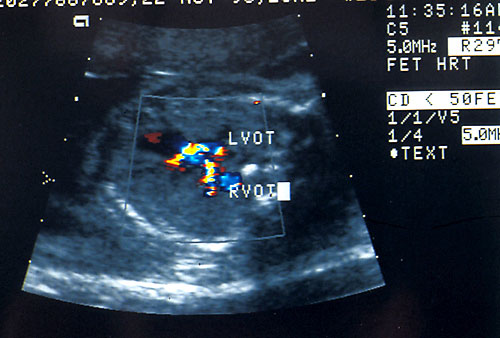

Color flow Doppler of fetal

heart to show cross over of

Left Ventricular Outflow Tract

(LVOT) and Right Ventricular

Outflow Tract (RVOT)

4. Color Doppler uses color-coded pulse Doppler on top of the B-mode ultrasound image. Color is usually assigned a direction. Usually blood flow toward the transducer is red and blue color is flow away from the transducer. Color saturation is relation to the magnitude of the frequency shift. (Carroll BA, von Ramm OT. Fundamentals of current Doppler technology. Ultrasound Q 1988;6:275) This allows the detection of small vessels and slower blood-flow velocity. Color flow imaging has the same limitations as pulsed Doppler.